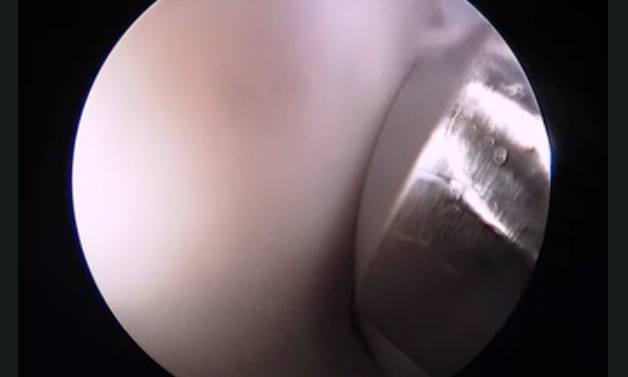

Discover the latest data supplements from Foot & Ankle International (FAI), the industry-leading journal for clinically-oriented research articles and therapeutic approaches in foot and ankle scholarship.